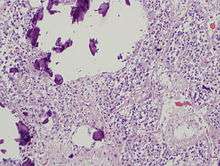

Histology

The pineal body consists in humans of a lobular parenchyma of pinealocytes surrounded by connective tissue spaces. The gland's surface is covered by a pial capsule.

The pineal gland consists mainly of pinealocytes, but four other cell types have been identified. As it is quite cellular (in relation to the cortex and white matter), it may be mistaken for a neoplasm.[14]